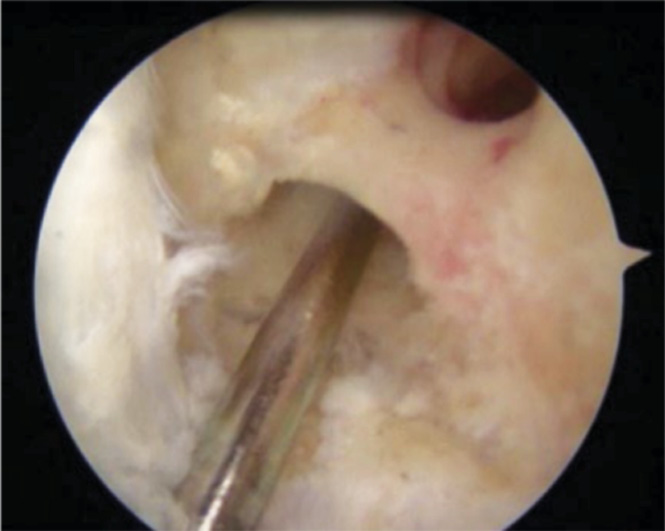

During the revision of ACL reconstruction, in 1 (1.1%) case, the location of the tibial channel was near the anterior horn of the internal meniscus (Figs. 4, 5).

Fig. 4. Location of the tibial canal near the anterior horn of the meniscus.

Fig. 5. Channel layout.